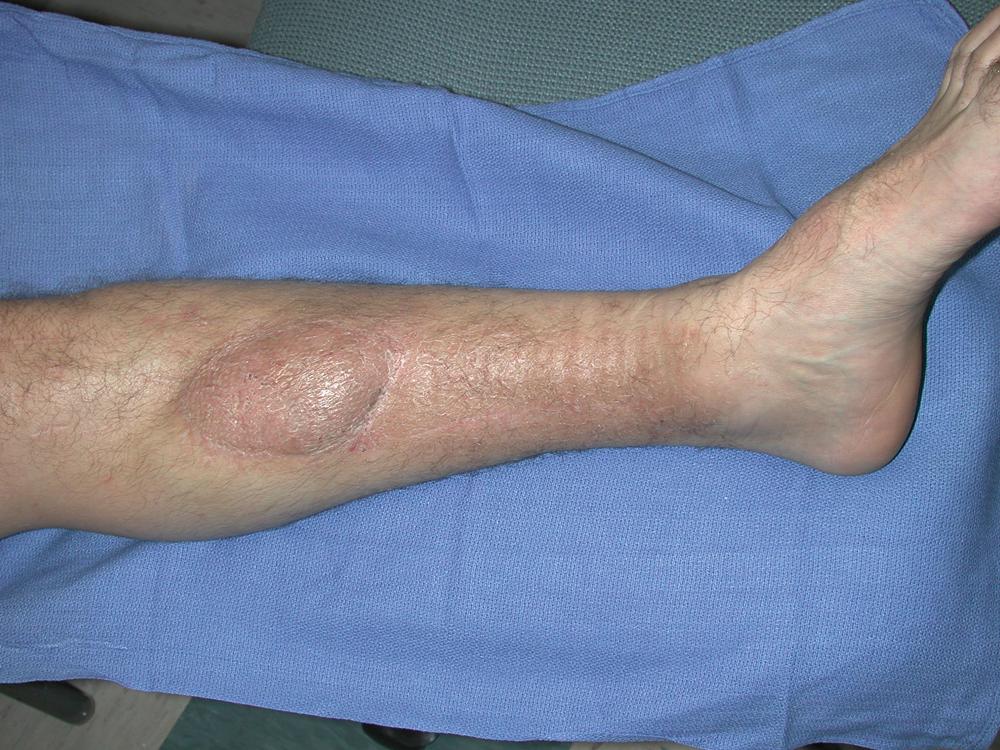

The patient did well postoperatively without any issues related to the flap reconstruction for the middle tibial wound closure. He was discharged from hospital on postoperative day 5. His left middle of leg wound healed uneventfully ( Fig. 44.8 ). He was followed by the plastic surgery service for routine postoperative care and underwent an autologous bone graft procedure by the orthopedic trauma service 2 months after flap reconstruction.

Fig. 44.8, Result at 5-week follow-up showing well-healed left middle-third tibial wound after the flap reconstruction.